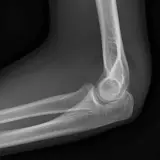

Over 2,100 interactive radiology cases, curated by radiologists for your level of training. Scroll, window, and view cases full screen โ€” just like on PACS. Click linked findings in each writeup to jump straight to them on the image. Cases include sample reports, a focused discussion section, original illustrations, and videos.

Casi completamente interattivi con gli strumenti che ti aspetti su un PACS: scroll, windowing, zoom, pan, misurazioni, ROI e modalitร  a schermo intero.

Annotazioni dettagliate evidenziano i reperti chiave direttamente sui casi. Clicca sui reperti collegati nella descrizione del caso per saltare alla loro esatta posizione sullo scan.